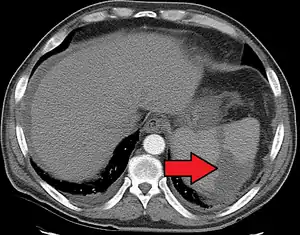

Splenic infarction

Splenic infarction is a condition in which blood flow supply to the spleen is compromised,[1] leading to partial or complete infarction (tissue death due to oxygen shortage) in the organ.[2] Splenic infarction occurs when the splenic artery or one of its branches are occluded, for example by a blood clot.[3]

| Splenic infarct seen on CT | |

An abdominal CT scan is the most commonly used modality to confirm the diagnosis,[3] although abdominal ultrasound can also contribute.[5][6][7]